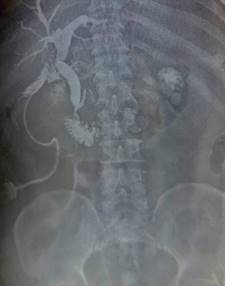

Masculino de 64 años, quien inicia su padecimiento con ictericia, negando otra sintomatología, llama la atención que se manifesta durante al menos tres días previos a su llegada a urgencias, su exploración física sin alteraciones, los laboratorios revelan una bilirrubina total de 25 mg/dl, bilirrubina directa de 22 mg/dl, fosfatasa alcalina 235 UI/l, gamma-glutamil transferasa 157 UI/l, creatinina 2.5 mg/dl, el resto de los laboratorios normales, se le realiza un ultrasonido de abdomen que reporta vesícula biliar mal definida, y dilatación de la vía biliar de 19 mm (Figura 1), se observa lito en colédoco de alrededor de 12 mm. Se integra el diagnóstico de coledocolitiasis, no obstante, se solicitan marcadores tumorales, con reporte de CA 19-9 de +8,000 UI; se solicita colangiorresonancia, la cual evidencia dilatación de vía biliar (vb) de 20 mm, lito de 16 mm a nivel del ámpula, no se reporta morfología de la vesícula biliar (VB), paciente candidato a colangiopancreatografía retrógrada endoscópica (CPRE) según el servicio de Gastroenterología. Se le realiza CPRE sin poder extraer lito, se programa para colecistectomía con exploración de vía biliar, el transoperatorio revela biliperitoneo, lisis de VB, fístula colecistocoledociana (Figura 2), litio único de 15 mm, se coloca sonda T, no se cuenta con servicio de cirugía hepatopancreatobiliar, por lo que no se realiza reparación definitiva, colangiografía transoperatoria revela paso de material de contraste a duodeno, sin fugas aparentes por orificio fistuloso (Figura 3), evolución posoperatoria favorable, el drenaje por sonda T en promedio 500 ml por día con disminución progresiva, con mejoría de hiperazoemia, con flujo urinario mayor a 0.5 ml/kg/h, colangiografía posoperatoria sin fugas, paso de medio de contraste a duodeno, reporte de patología revela adenocarcinoma de vesícula moderadamente diferenciado con infiltración a muscular (Figura 4). El paciente rechaza tratamiento médico y decide egreso voluntario, comprende y acepta los riesgos, no contamos con seguimiento a largo plazo.

El diagnóstico preoperatorio es difícil en general, éste suele sospecharse en pacientes mayores con dolor en hipocondrio derecho y síntomas atípicos. El ultrasonido es poco sensible para detectar hallazgos, pues posee una precisión tan baja como 11% en algunas series reportadas. Algunos autores mencionan datos sugestivos para SM: VB atrófica, dilatación del CH con VBC de calibre normal (92%). Otros datos indirectos son: dilatación de la VBC mayor a 7 milímetros, con o sin lito mayor a 10 mm en VBC, neumobilia, lito enclavado en Hartmann.7

En caso de CAVB, las calcificaciones invasión luminal, pérdida de la interfase hígado-vesícula, infiltración hepática directa, pared irregular, pólipo vesicular mayor a 10 mm, son los hallazgos conocidos.3 El ultrasonido carece de utilidad para valorar el estadio, es decir, la extensión de la enfermedad.